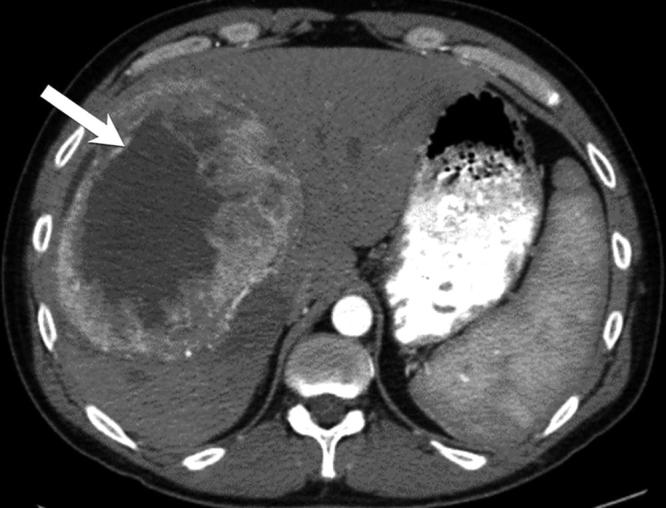

CT classically demonstrates a large, marginated, heterogeneous hypodense mass with internal and peripheral enhancement (Figure 13). A cystic mass with an enhanced thickened wall has also been reported, which may mimic an abscess or hydatid cyst.49 On MRI, it shows homogenous or heterogeneous hypointensity on T1 weighted images, and hyperintensity on T2 weighted images. Lack of enhancement in the arterial and venous phases followed by marked enhancement on the delayed phase has been reported and may be a useful finding.50

Figure 13.

Leiomyosarcoma: axial contrast-enhanced CT showing a large heterogeneously enhancing predominantly hypoattenuating mass (arrow) occupying the right hepatic lobe. This was pathologically proven to represent leiomyosarcoma.